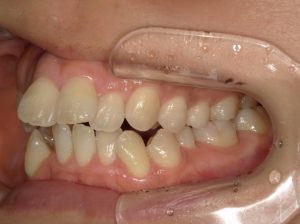

治療前→治療後(右側方)

治療前→治療後(左側方)